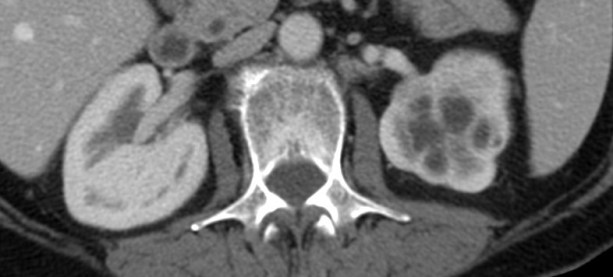

Tomografía computarizada:

Es más sensible que la ecografía y constituye la técnica de elección para detectar las calcificaciones y resto de hallazgos de la TBC renal gracias a la administración de contraste intravenoso.

Como siempre, los hallazgos varían según la afectación sea:

Estadio final:

- Hidronefrosis progresiva con disminución del parénquima renal que puede simular quistes. Sirven como apoyo diagnóstico la positividad a los cultivos.

- Atrofia renal con calcificaciones que afectan a todo el riñón. Las calcificaciones extensas en un riñón no funcionante (autonefrectomía) es lo que se denomina como riñón mastic.

Los hallazgos descritos no son específicos y pueden verse en otras entidades. Sin embargo la combinación de 3 o más de los siguientes hallazgos son altamente sugetestivos de TBC renal incluso con ausencia de afectación pulmonar:

- Cicatices.

- Retracciones del sistema colector.

- Necrosis papilar.

- Masas de baja atenuación.

- Calcificaciones